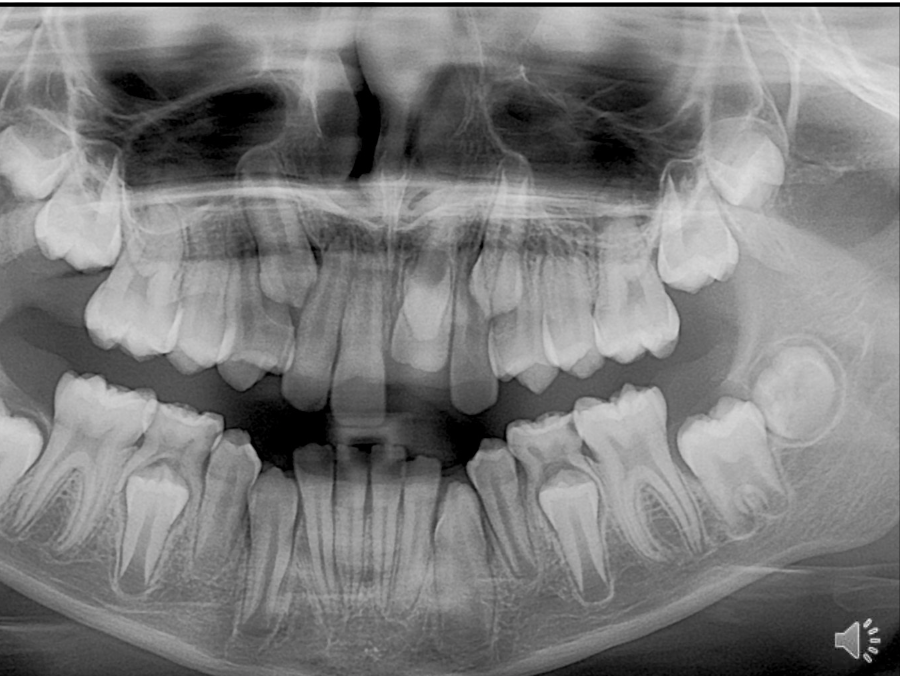

Lower right quadrant- two molars each with two roots, and two premolars, crown not as wide as molar and have a single tapering root

Maxillary central incisors- enamel is thinner on incisors compared to molars, broader canal and a single conical root

for mandibular teeth, apex/ root points upwards and crown points downwards- mandibular teeth are opposite rotation